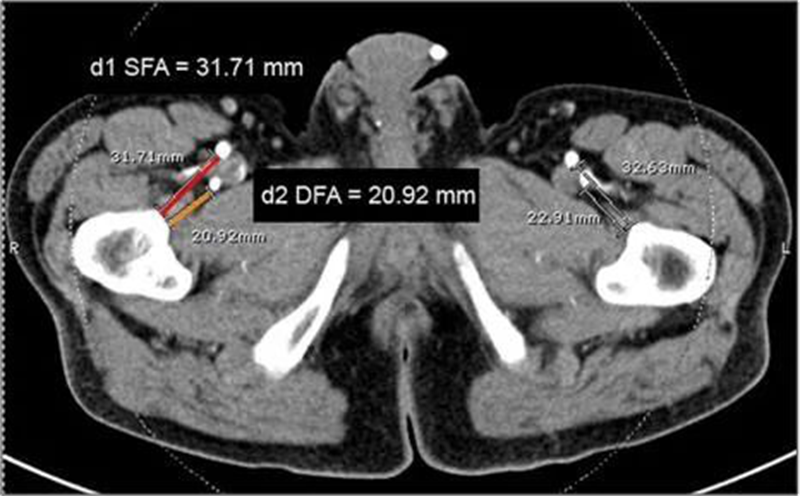

图2 轴向CTA用于确定股骨皮质与SFA(d1)和DFA(d2)之间的最短距离

该研究采用带有 3D 重建的轴向 CT 扫描以识别股浅动脉(SFA)和 股深动脉(DFA)相对于股骨干皮层的位置,把股骨内侧划分成8个部分(A-H),股骨的长度从大转子尖端到胫股外侧关节线的长度,分为8等分(7级)。

在手术过程中,必须透视确定小转子的下边缘。我们遵循他们的股骨截面图,说明了股骨皮质与SFA 和 DFA 之间距离的测量,但我们感兴趣的区域是从大转子尖端到外侧胫股骨的整个股骨长度联合线。使用这些位置参数可以帮助外科医生在手术过程中更轻松、更准确地识别股骨上的特定感兴趣区域。